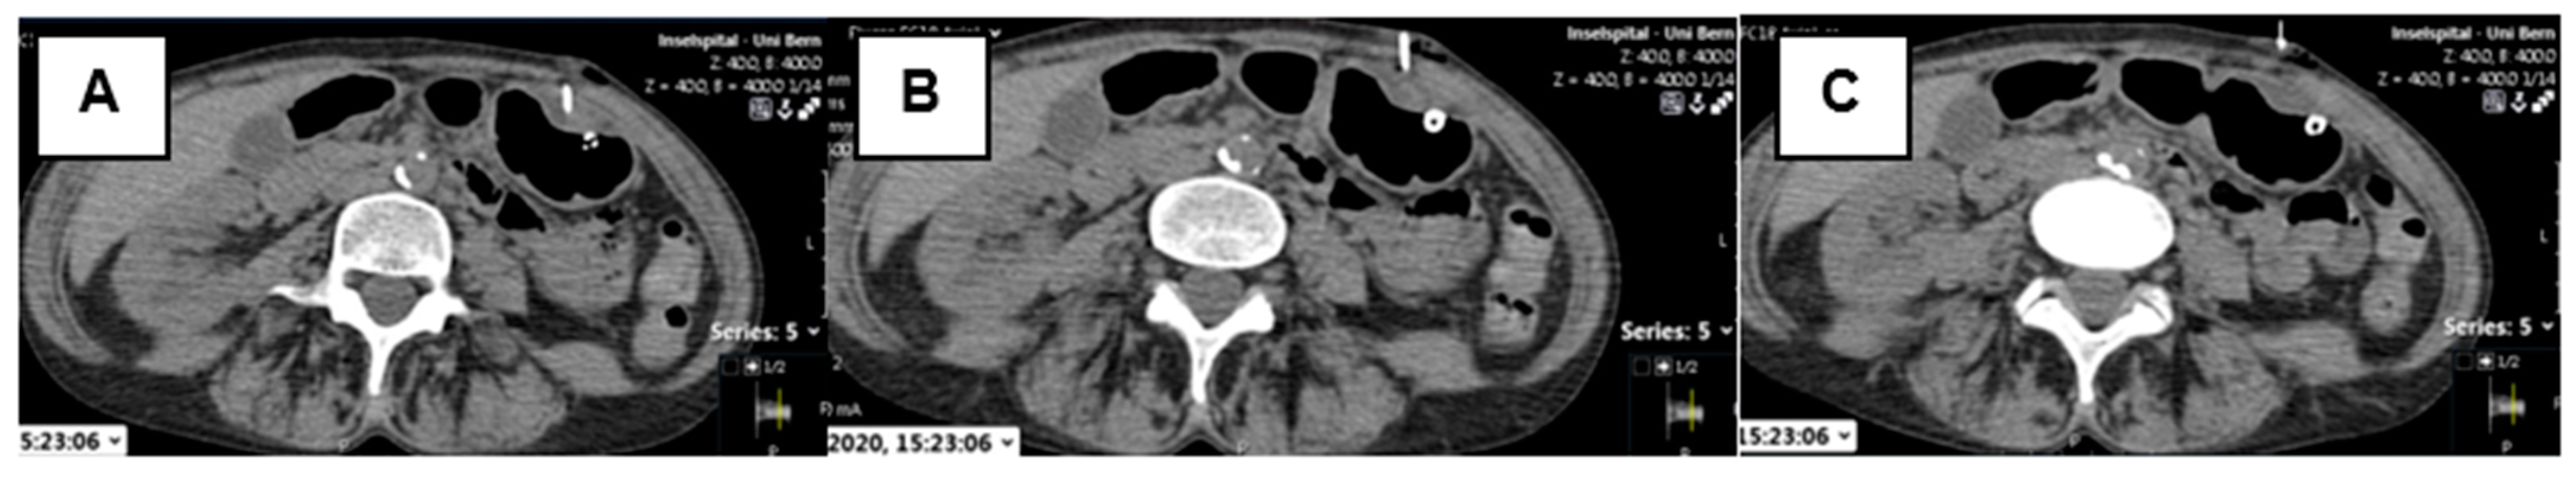

2.3. CT-Guided PRG Technique